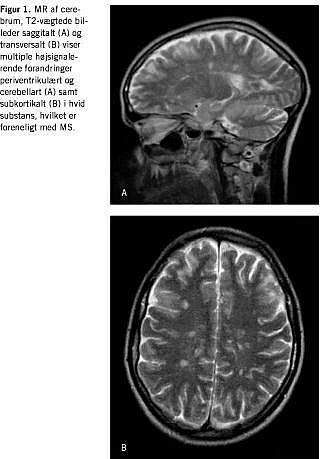

Akut neurologisk blev patienten udredt med CT af cerebrum to gange, hvilket ud over cerebellar atrofi intet abnormt viste. Der blev foretaget spinalvæskeundersøgelse, hvor der fandtes normalt celletal, normalt spinalprotein og -glukose og ingen xantokromi. Som led i den videre neurologiske udredning blev der foretaget MR-skanning af cerebrum, hvilket viste multiple white-matter-lesions periventrikulært, subkortikalt og infratentorialt, hvilket er foreneligt med MS (Figur 1 ). En supplerende spinalvæskeundersøgelse viste forhøjet IgG-indeks og tydelig oligokloni. Visual evoked potentials (VEP) var med normale VEP-latenser bilateralt.